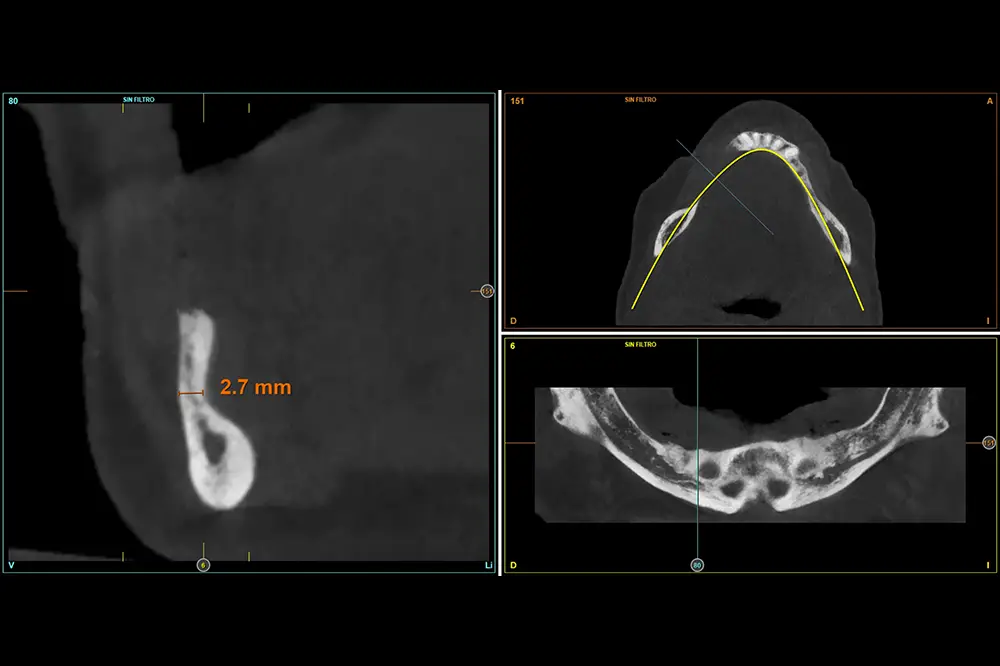

Figuras 12-15. En el cuarto cuadrante, la situación es muy similar, planificándose de nuevo implantes de 2,5 mm.